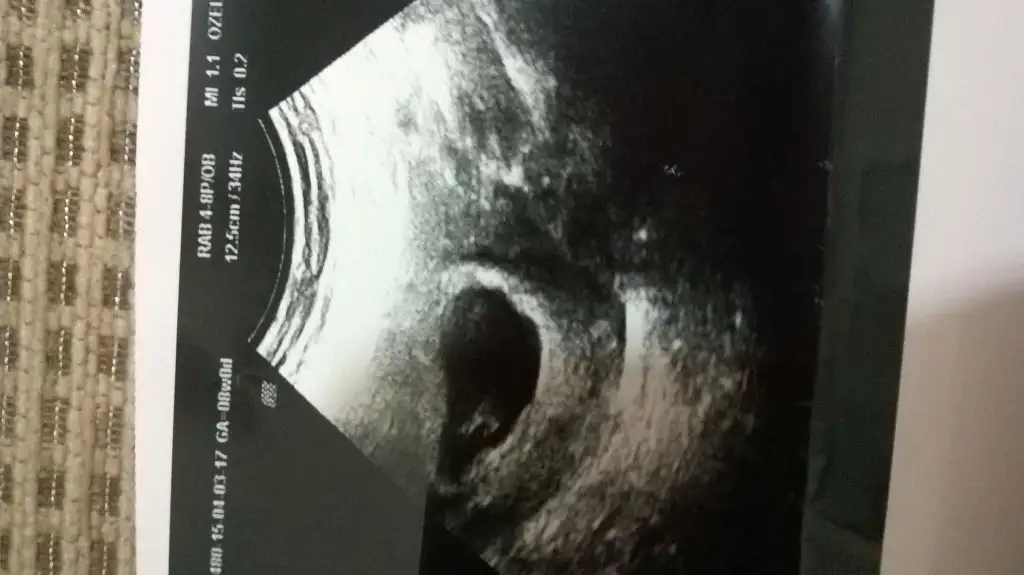

Çok sevindim. Darısı başıma, bende duyarım inşallah. Bugün testte tam netti çizgi. Bende hamileyim:). Ama korkunç bel ağrım var. Herşey yolundamıdır???Kızlar çok şukur kalp atışını duydum bugün...dr her şey yolunda dedi şimdi foto gonderecem bakalım tahmin varmı

Erkek istiyodun degilmi?? Bana erkek gibi cunku geldi....Umarım inşallah...şimdi fotı yükledim bakalım yorumlayabilen varmı

gözün aydın canım rabbim gönlüne göre versin...Kızlar çok şukur kalp atışını duydum bugün...dr her şey yolunda dedi şimdi foto gonderecem bakalım tahmin varmı

atmaya çalışayım canım....asosyalci canım foto at varsa yorum yaparız belki